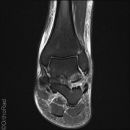

Snowboard fracture Talus